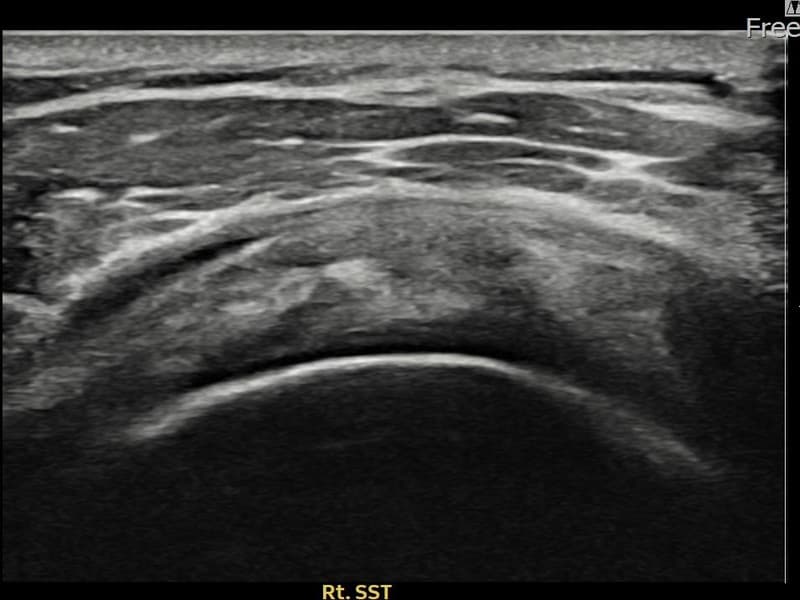

施術後

術前超音波にて右 견갑하근건 関節面側部分断裂・右肩棘上筋腱のエコー不連続と腱欠損(7mm × 3mm (腱厚の約28%欠損))を確認。術後超音波では断裂部位が再生組織で充填され、腱の連続性回復とエコーパターンの正常化が確認されました。

持続する右肩痛で来院された患者様です。超音波検査にて右 견갑하근건 関節面側部分断裂(欠損:7mm × 3mm (腱厚の約28%欠損))を確認し、超音波ガイド下で非手術的縫縮術を施行しました。術後は約4〜6週間のブレース装着の後、段階的なリハビリプログラムを実施。経過超音波で腱の連続性回復を確認し、患者様は無事に日常生活へ復帰されました。